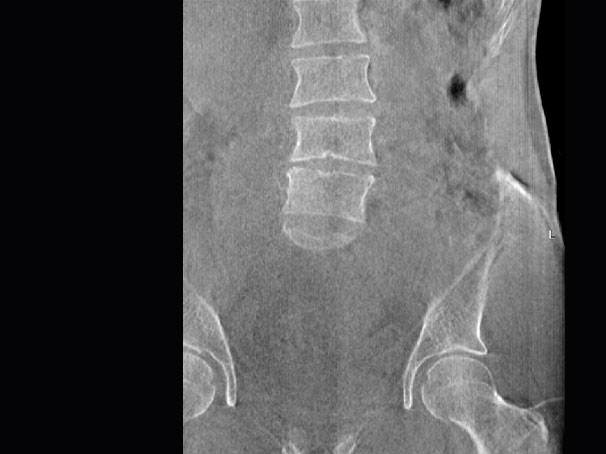

• 髖關節

支持雙腿或雙側髖關節掃描 | 方便對比,降低漏診誤診

FOV 250mm

FOV 350mm